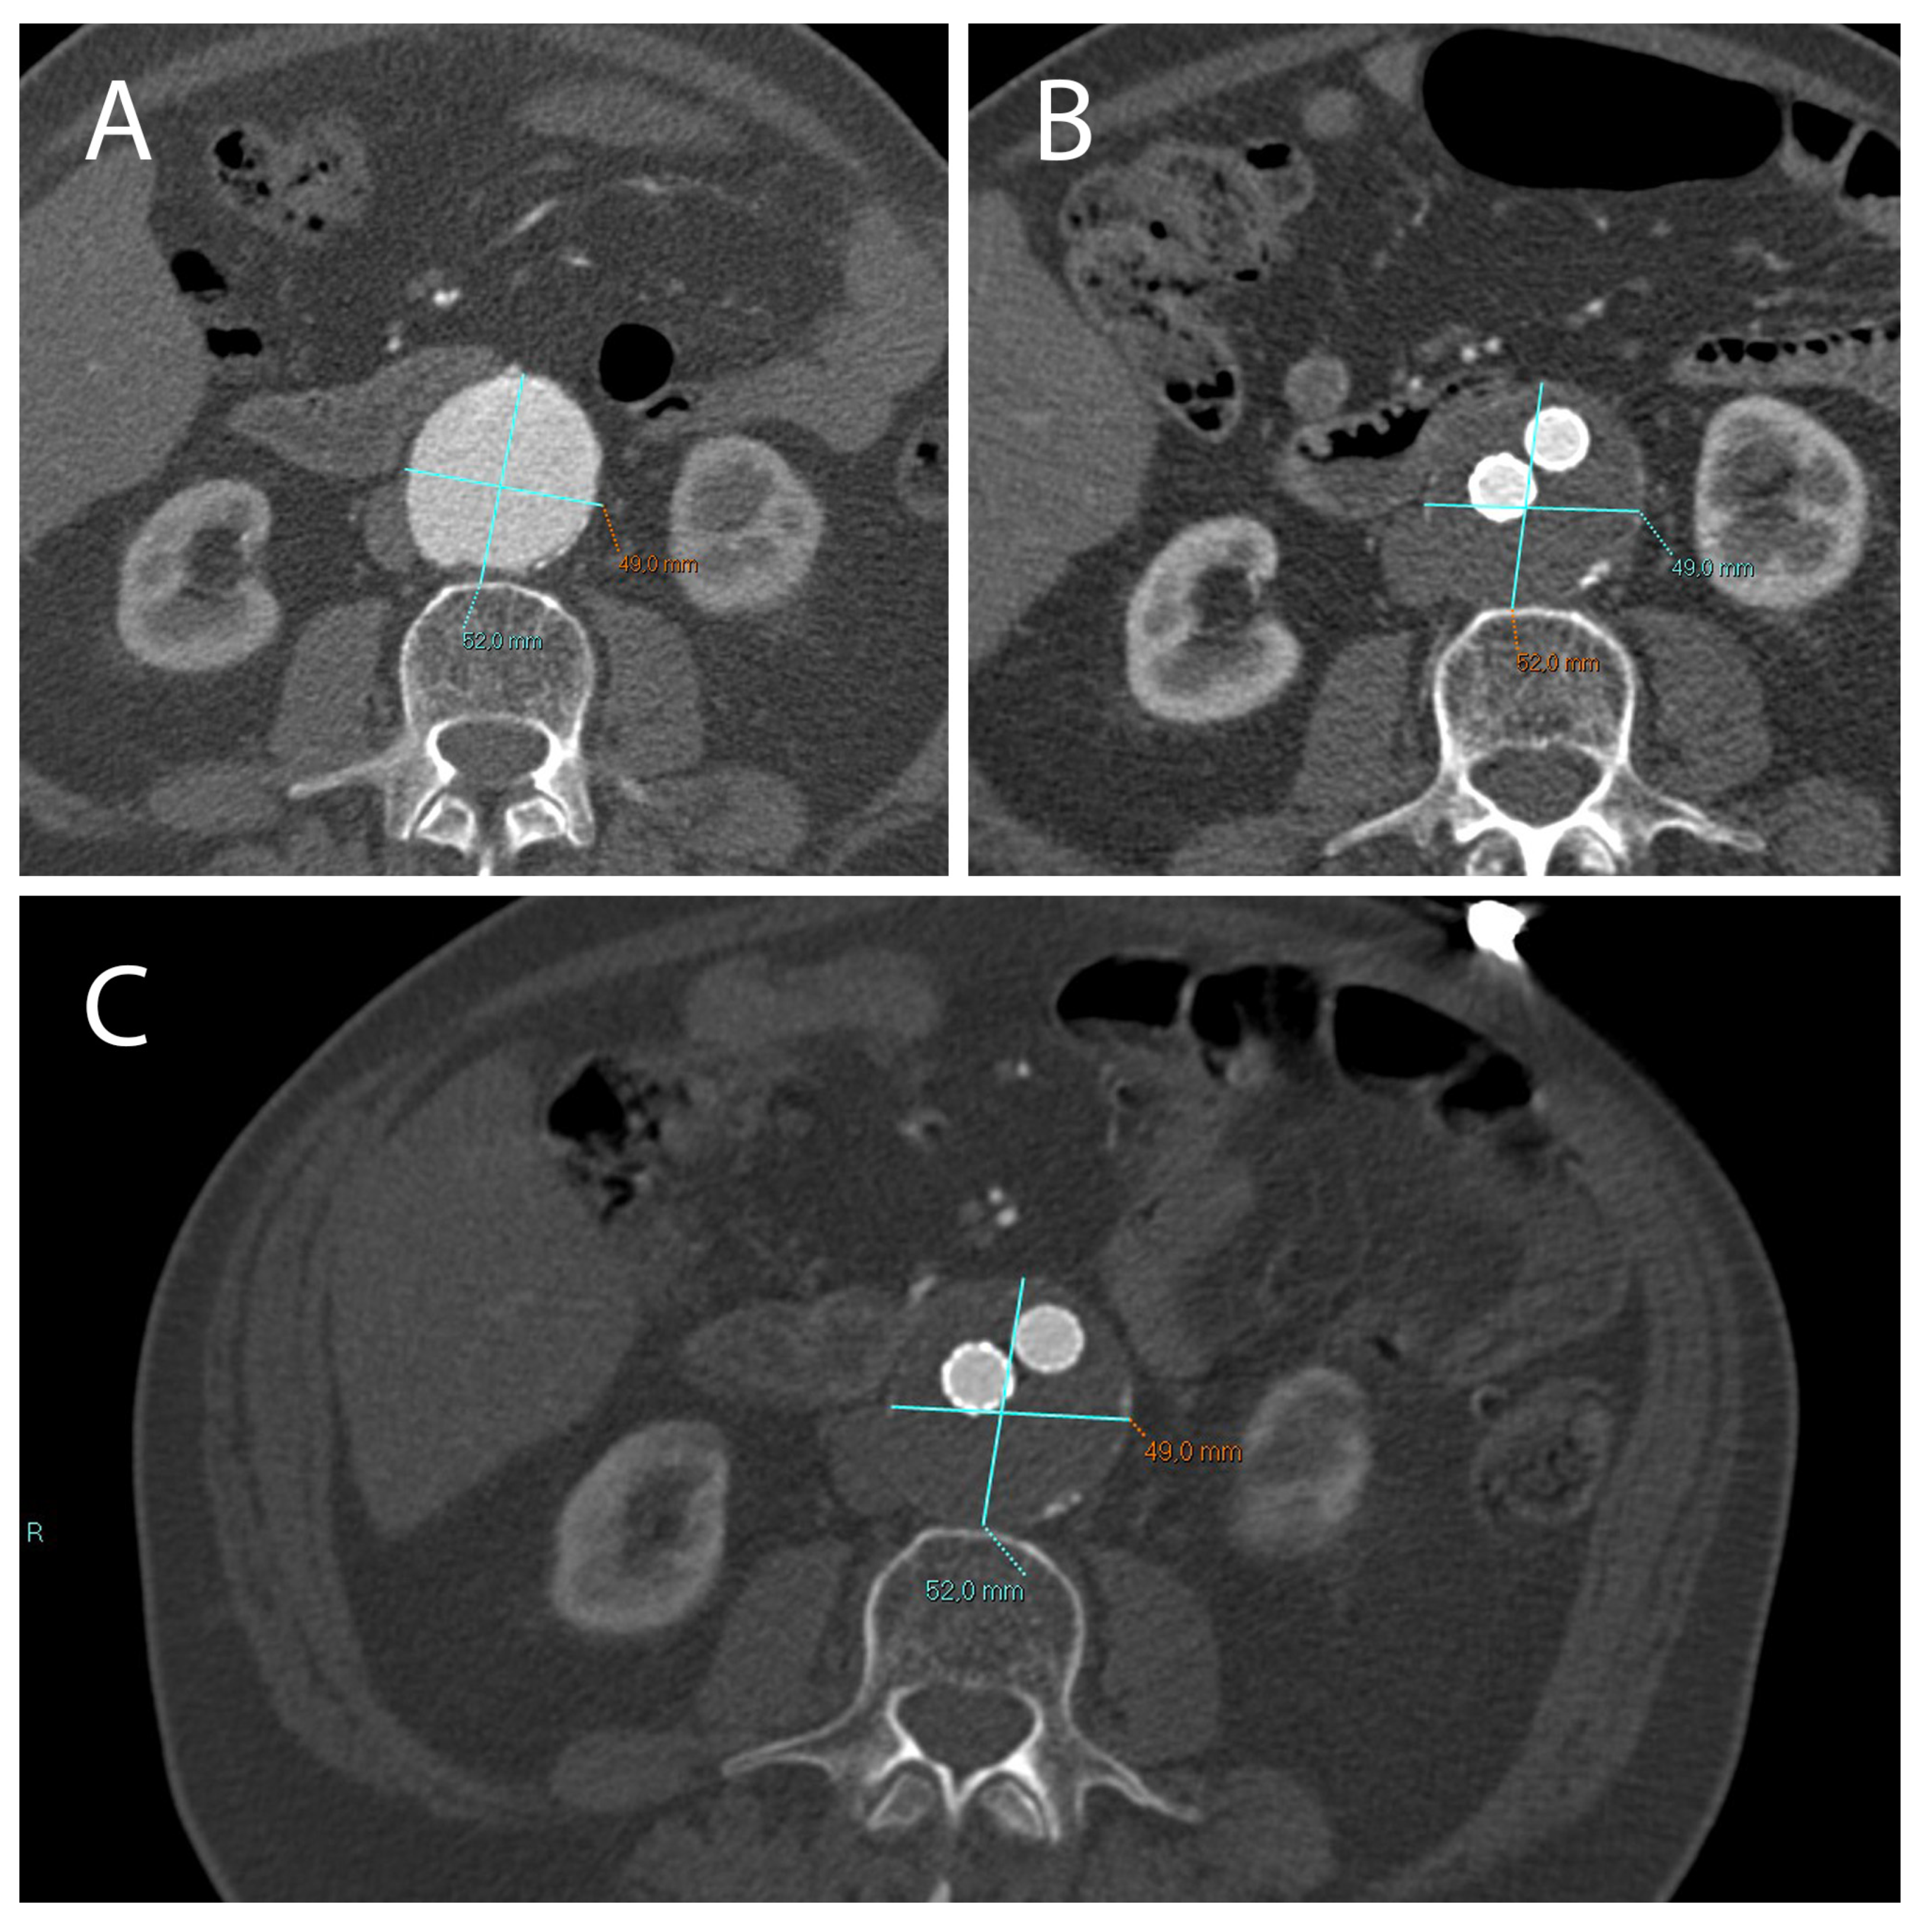

2.1. A Stable Aneurysm Diameter Is Associated with Persistence of Endoleaks